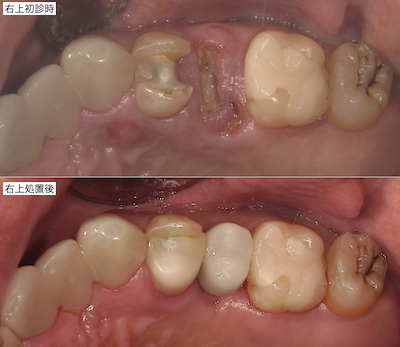

各々の部分の比較です。まず右上です。

アンカースクリューによる右上の圧下も終えて、上部構造を装着しました。

上部構造装着後です。